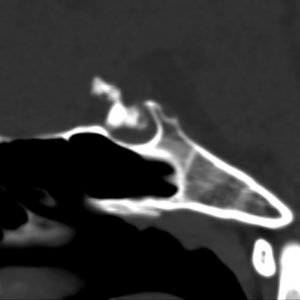

クラニオの骨化 ossification

なぜ気にするかというと手術がとても難しくなるからです

- 石灰化はよくありますし,石灰化が手術で問題となることはありません

- 骨化は似て非なるものです

- 石灰化は砕けますが,骨化は砕けないので一塊にして引きずり出すことになります

- この操作によって,手術リスクが極めて高くなります

生涯で最も苦労した例:骨化をなめてはいけない!

11歳で低身長で発症しました。左のCTでは小さな骨化に見え,この程度の頭蓋咽頭腫なら何とかなると思っていました。しかし手術所見では,視交叉や視床下部底部から剥離できない,ものすごく硬い骨化でした。骨化部分が動かせないために,周囲の穿通枝(動脈)とも容易にははがれませんでした。開頭術だったのでソノペットで骨化を破砕しましたが,視交叉を少し損傷しました。何とか全摘出でき汎下垂体機能低下症の治療しています。でも再発なくて,元気に学校似通って水泳とか吹奏楽コンクールにでているそうです。

鞍上槽の骨化例

8歳の女の子です。学校の検診で両側の視力低下を指摘されて,その4ヶ月後にようやく頭蓋咽頭腫が発見されました。発見されたときは,両耳側半盲で高度の視力低下(左指数弁)でした。

とにかく残った視力を助けなければならないので,まず,熟練した術者に経蝶形骨洞手術でのう胞除圧(のう胞から液体を抜く手術)をしていただきました。下垂体機能は温存されました。なんとか両側の失明は防げたのですが,視力と視野は改善しませんでした。このような頭蓋咽頭腫では一度悪くなった視力と視野は手術しても改善しないことが多いです。

視神経への圧迫はとれたので,今度は腫瘍の本体を摘出しなければならないのですが,トルコ鞍上部に大きな骨化(黄色の矢印)があります。骨化は15mmくらいの大きさがありました。この大きな骨化は砕くことができずに,周囲を全部剥離して一塊にして引きずり出しました。後交通動脈の下側から引っ張りだしたのですが,かなり危険な手術操作でした。結果的には,下垂体柄を温存できて腫瘍を全摘出しました

鞍内の骨化例

14歳で低身長で発症していますから,かなりゆっくり増大した鞍隔膜下頭蓋咽頭腫です。トルコ鞍内・鞍隔膜下に骨化があります。経鼻的手術で全摘出しました。下垂体柄と下垂体はなんとか形態的温存をしています。